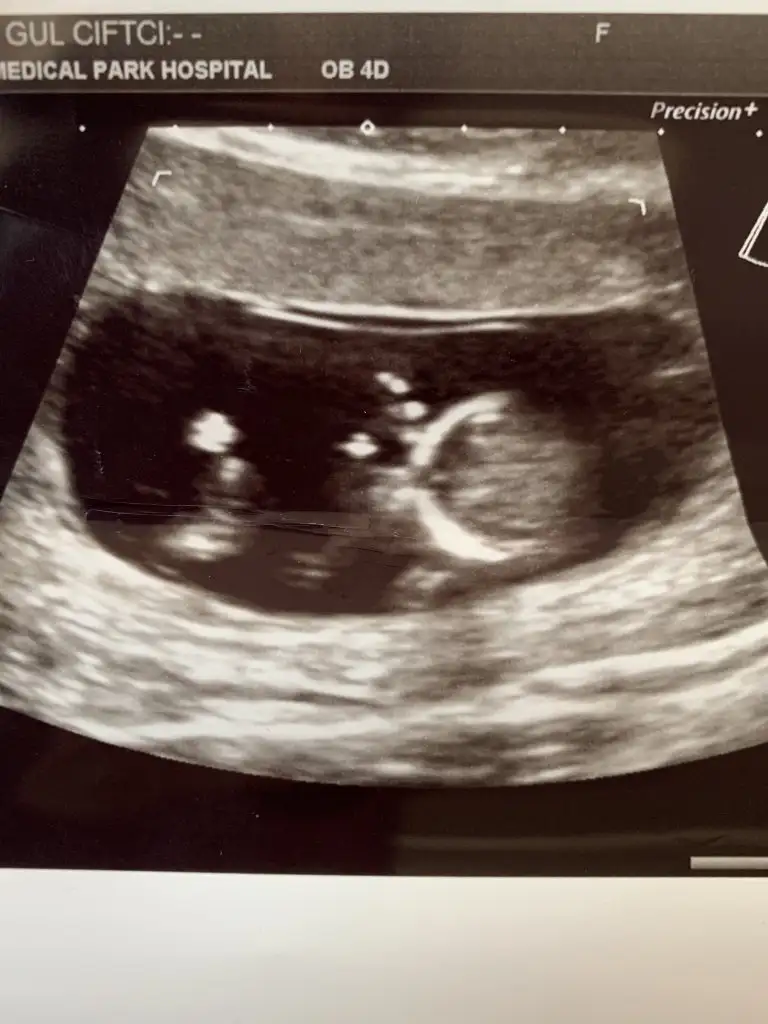

dr soylemeden siz gorun genital nub teorisi ( bebegin cinsiyeti)

Banada tahminde bulunabilir misinizzz🥰

Eklentiler

• 3885AD85-6BBA-4800-82D2-A71289D3C3C0.webp

3885AD85-6BBA-4800-82D2-A71289D3C3C0.webp

22,7 KB · Görüntüleme: 57